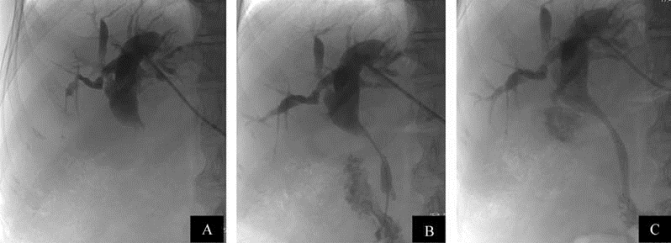

图21-35 经皮肝穿刺胆管引流(PTCD)

A.肝内胆管扩张,肝总管及胆总管上段狭窄呈细线状,胆总管下段正常;B.同时行支架内引流和置管外引流;C.1周后复查,肝内胆管扩张情况已大为改善,外引流置管可拔除